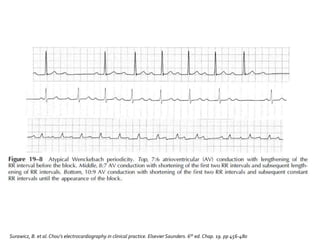

 Se caracteriza por la prolongación sucesiva

del intervalo PR hasta que una onda P se

bloquea

 Fenómeno deWenckebach

 La onda P regresa a su valor de base y la

secuencia comienza de nuevo.

 El máximo incremento en la prolongación del

intervalo PR ocurre entre el primero y el

segundo ciclo

 En los ciclos subsiguientes el incremento es

cada vez menor

 Acortamiento de los intervalos RR a partir de

la pausa que sigue al latido de escape

 El ciclo largo (que contiene el latido de

escape) es menos de dos veces el ciclo más

corto

Incremento progresivo del PR

Intervalos R-R progresivamente menores

Pausa entre los complejo QRS de la onda P no

conducida que es menor a la suma de dos

intervalos R-R

Acortamiento del intervalo PR después del

bloqueo, comparado con el PR previo al

bloqueo